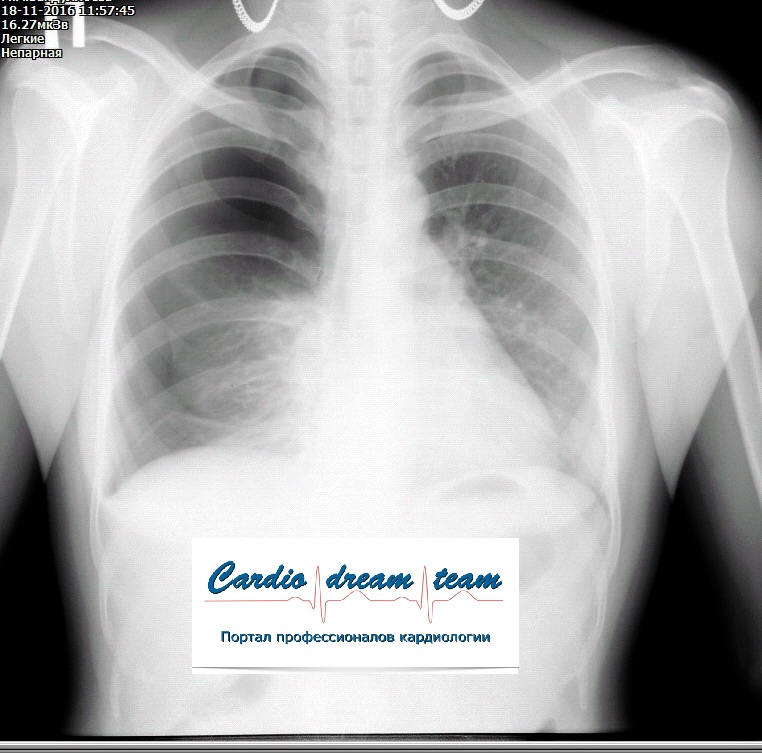

Проведена рентгенография органов грудной клетки в прямой проекции, положение полусидя, условия ПИТ, Р-контроль Легочные поля: Отрицательная динамика: правое легкое поджато к корню. Тень средостения резко смещена влево. Выраженная подкожная эмфизема мягких тканей грудной клетки справа. Тень подключичного катетера в проекции ВПВ. Легочный рисунок: диффузно деформирован за счет пневмосклероза, сгущен справа Корни: тень средостения смещена влево Синусы: нечеткие Сердце: широко лежит на диафрагме (позиционно) ЗАКЛЮЧЕНИЕ: Правосторонний пневмоторакс, отрицательная Р-динамика. Эмфизема мягких тканей грудной клетки. Пневмосклероз. Р-контроль.